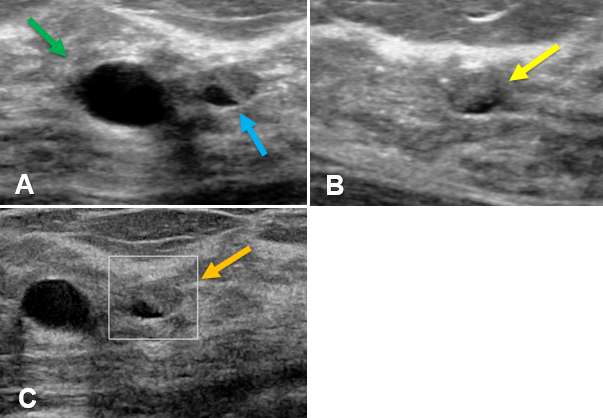

Ultrasound - Ultrasound is a particularly useful modality to evaluate breast cysts due to its ability to differentiate fluid-filled cysts from solid masses. Simple cysts appears as well-circumscribed, anechoic, round or oval structures, with thin walls that demonstrate posterior acoustic enhancement. Simple cysts can often be moved or compressed with the ultrasound probe which can help distinguish cysts from solid masses, which are usually immobile. Additionally, simple cysts do not exhibit vascularity nor contain internal echoes or solid components.

Ultrasound - On ultrasound, clustered microcysts display features similar to simple breast They typically appear as a group of small (2-3 mm) anechoic foci with thin (<0.5 mm) intervening septa and without a discrete solid component. Clustered microcysts also demonstrate posterior acoustic enhancement, similar to simple cysts. The margins of a clustered microcyst may be microlobulated but are well-defined.

Ultrasound - On ultrasound, complicated cysts appear as round or oval lesions with thin walls, homogeneously hypoechoic internal debris, and may exhibit fluid-debris levels and low-level internal echoes that can change the shape of the cyst with changes in patient positioning. The internal debris may appear as hyperechoic components that adhere to the cyst wall and careful examination with power Doppler should be performed to exclude vascularity which would indicate a solid component. Complicated cysts may or may not exhibit posterior acoustic enhancement depending on the make-up of its internal components. The walls of a complicated cyst are often slightly thicker than that of simple cysts due to inflammation or mild fibrosis which can occur due to the internal proteinaceous or hemorrhagic components.